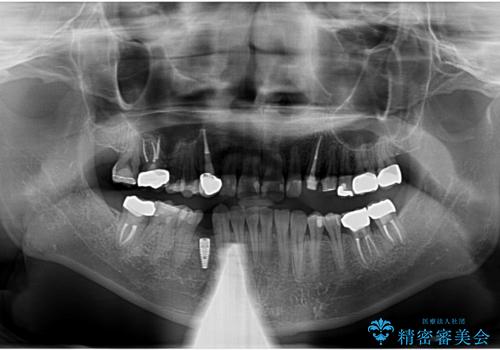

- 長年虫歯の治療を受け続けたことで銀歯・コンポジットレジン修復だらけになってしまい、今後の見た目や歯を大切にするためにセラミック治療矯正治療を希望され来院されました。

マイクロスコープを用いた精密根管治療やセラミック治療、マウスピース矯正治療を一つの医院で行うことのできる当法人ならではの総合歯科治療を実践していきます。

- 約330万円 (セラミック治療 矯正治療 インプラント治療含む)費用は治療当時の料金となります